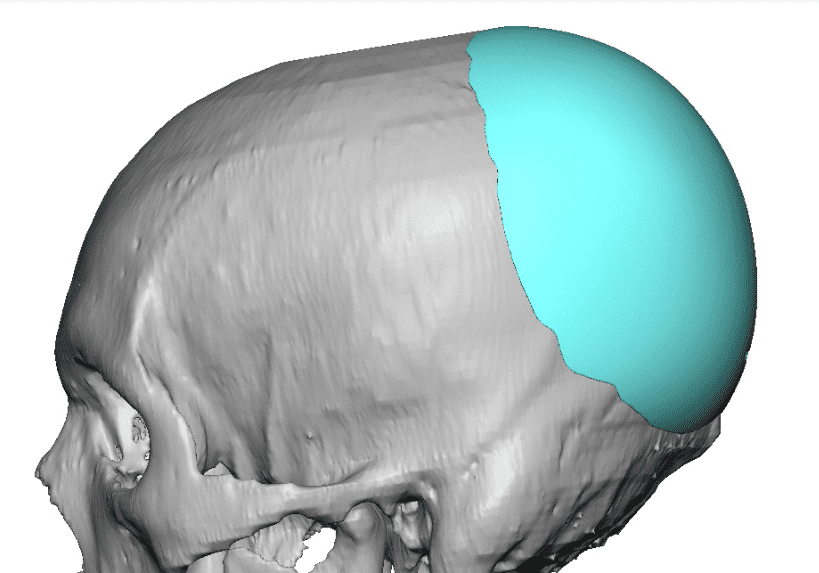

Desire for an improved head shape so that it looks rounder and not so peaked or sloped.

Placement of custom skull implant for parasagittal augmentation to create a rounder head shape. An example of what appears to be a high sagittal crest that is really low parasagittal skull areas.

Desire for an improved head shape so that it looks rounder and not so peaked or sloped.

Placement of custom skull implant for parasagittal augmentation to create a rounder head shape. An example of what appears to be a high sagittal crest that is really low parasagittal skull areas.